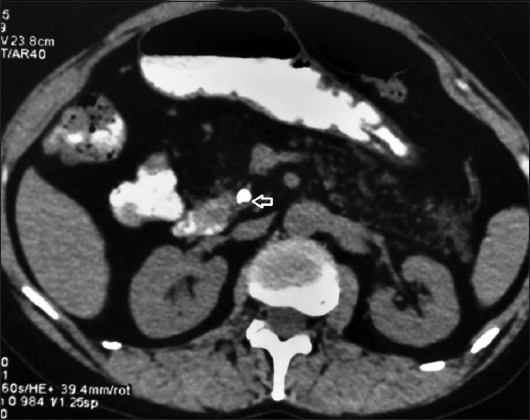

Background: Fatty changes in the pancreas are common, whereas total pancreatic lipomatosis (PL) is rare. Commonly associated with various components of metabolic syndrome and metabolic-associated steatotic liver disease, total PL can have various etiologies and can manifest with severe pancreatic exocrine insufficiency.

Method: We retrospectively analysed the clinical profile and management outcomes of 8 patients (mean age: 37.1 years; 5 male) with total PL seen at a tertiary care center over the last 15 years.

Results: All patients presented with abdominal pain and had coexistent chronic pancreatitis, while 5/8 (62%) patients had metabolic syndrome. None of the patients had a history of acute pancreatitis or congenital syndromes, nor developed pancreatic carcinoma in the follow up. Seven (87%) patients had pancreatic ductal dilatation and calcification. All patients had pancreatic exocrine insufficiency, while 5/8 (52%) patients had endocrine insufficiency. Six (75%) patients were successfully managed with pancreatic endotherapy.

Conclusions: Pancreatic endotherapy is safe and effective in the treatment of abdominal pain in patients who have chronic pancreatitis with total PL. These patients have a high frequency of pancreatic exocrine as well as endocrine insufficiency.